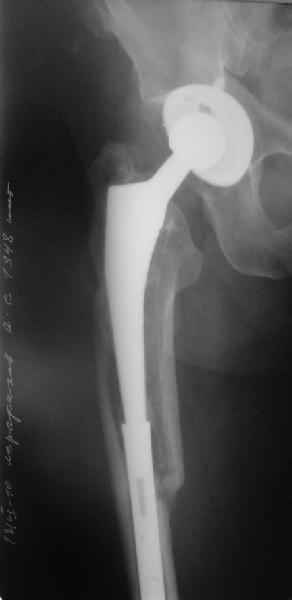

Произведено закрытое удлинение ножки эндопротеза с помощью ретроградного интрамедуллярного стержня. Продолжительность операции 3 часа. Два из них закрытое восстановление длины бедра диистрактором

таз-бедро.

А нельзя ли увидеть и профиль бедра на всем протяжении, т.е. и весь протез, и весь стержень? И фас бы с коленом.

новые снимки

Пациента удалось осмотреть недавно. Достигнутый результат сохраняется. Перелом бедра сросся. Конечность опорная и безболезненная, ходит без трости. Ножка, похоже, реинтегрировалась, как и надеялись. Снимки и фото в приложении. Комментарии приветствуются.

Надо ли что-то делать дальше, как полагаете? Убрать винты? Убрать "удлинитель ножки"? Или оставить все, как есть? Спасибо заранее.